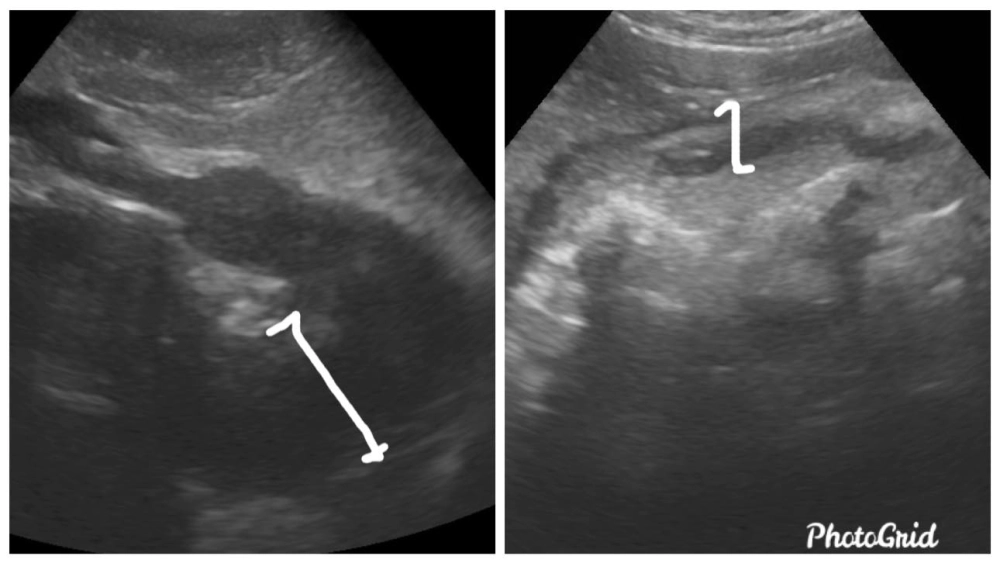

(左)治療前之胃壁,明顯增厚,也造成嘔吐,胃排空不良等症狀,導致貓咪厭食。 (右) 化學治療後之胃壁,厚度,分層較恢復正常,也恢復容納食物與排空的功能。